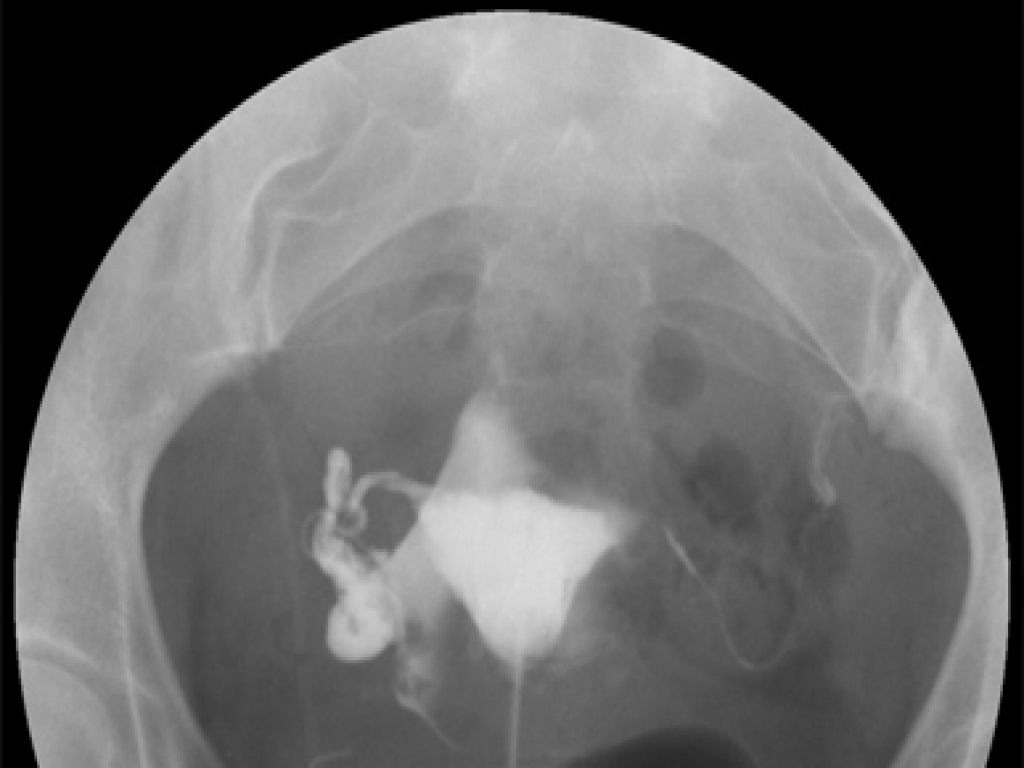

Rahim filmi, rahim ve fallop tüplerinin yapı ve fonksiyonlarını değerlendirmek için kullanılan bir radyolojik testtir. Resmi adı "histerosalpingografi" olan bu test, genellikle infertilite (kısırlık) sorunu olan kadınlarda kullanılır. İşte rahim filmi hakkında daha fazla bilgi:

Testin Amacı: Rahim filminin temel amacı, rahim ve fallop tüplerinin iç yapısını ve geçirgenliğini görselleştirmektir. Bu sayede rahim içi anormallikler, tüplerin tıkanıklığı veya diğer yapısal sorunlar hakkında bilgi edinilebilir. Bu bilgiler, kısırlık nedenlerini belirlemek ve uygun tedavi yöntemlerini planlamak için önemlidir.

Nasıl Yapılır: Rahim filmi genellikle radyoloji veya rahim hastalıkları uzmanı tarafından yapılan bir işlemdir. İşlem sırasında, rahim ağzından bir kateter (ince tüp) yerleştirilir ve rahimin içine kontrast madde enjekte edilir. Kontrast madde, rahim ve fallop tüplerinin röntgen görüntülerinin daha net olmasını sağlar. Röntgen cihazı kullanılarak, rahim ve tüplerin iç yapısı ve geçirgenliği görüntülenir.

Sonuçların Değerlendirilmesi: Rahim filminin sonuçları, radyolog veya rahim hastalıkları uzmanı tarafından değerlendirilir. Bu sonuçlar, rahim içinde anormallikler, tüp tıkanıklığı veya diğer yapısal sorunlar hakkında bilgi sağlar. Bu bilgiler, ilgili tedavi seçeneklerinin belirlenmesine ve infertilite sorununun çözülmesine yardımcı olur.